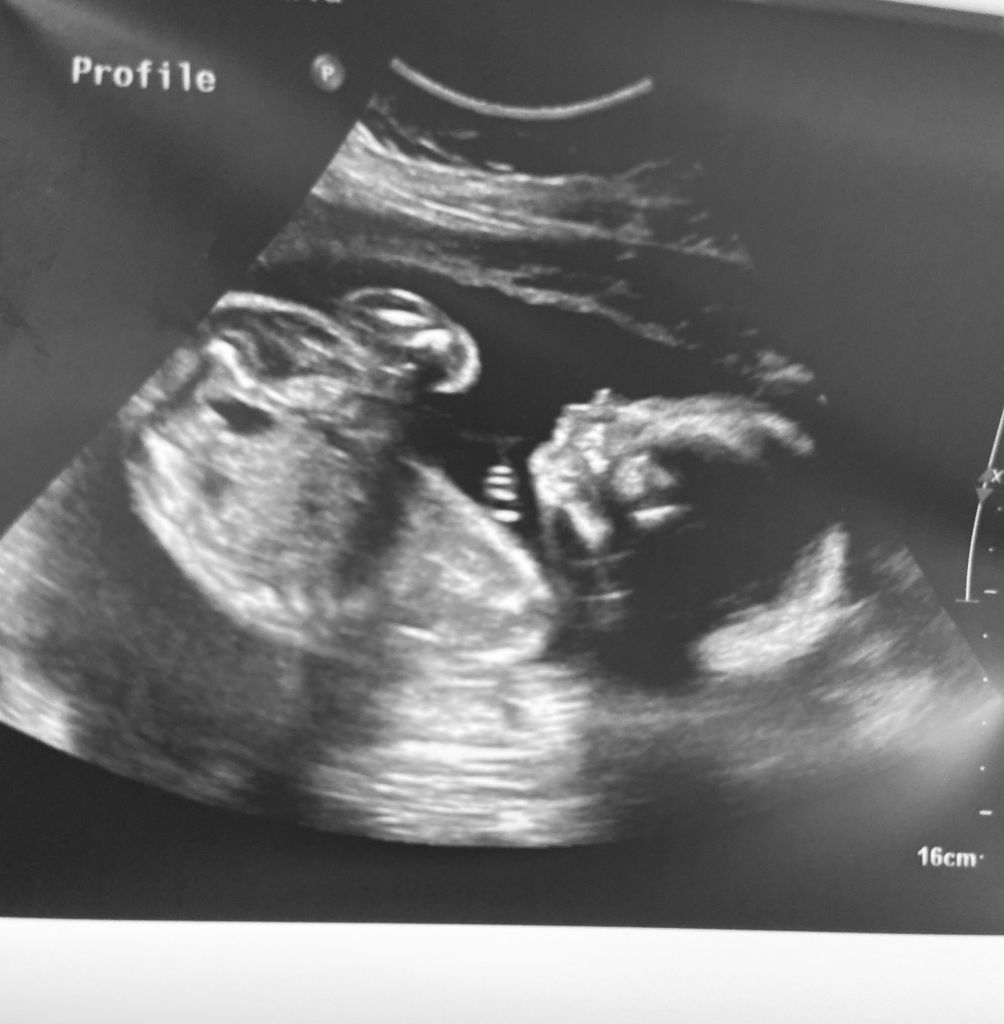

So, why does it happen? We asked a real-life couple to weigh in on their nesting experience as they prepare for their baby boy, Dean, to make his grand entrance. Hailing from Newton Falls, Ohio, learn more about Sonia and Adam’s POV during their crazy ride!

Q: How far along are you, Sonia?

Sonia: 34 wks, 1 day

Q: When is Dean expected to arrive? Do you have a birth plan?

Sonia: Due date is March 15th, 2022 and natural birth. However, due to health issues, he might come a little sooner than March 15th!